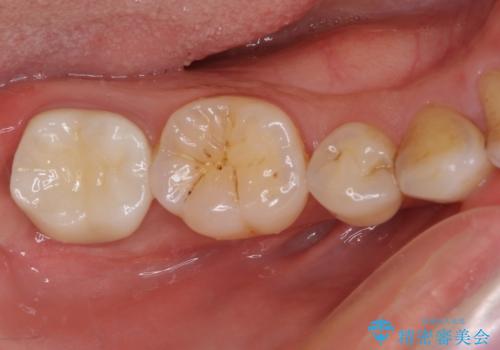

どちらの歯も痛みなどの症状はなく、治療後も異常所見なく経過をたどっています。

上顎大臼歯は向かい合った人から見えることはほとんどないため、切削量が少なく、適合の良いゴールドインレーが大変おすすめとなります。